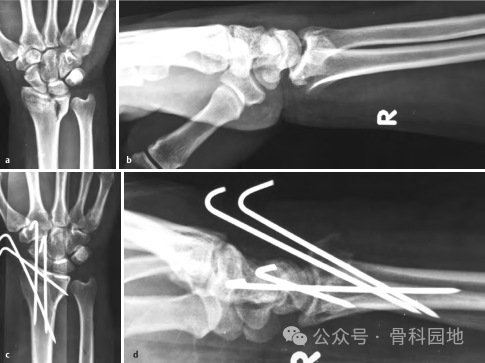

使用经典经皮克氏针固定桡骨远端骨折,如下图a-e 。

采用经皮克氏针固定后手指运动情况,如下图a-d 所示。